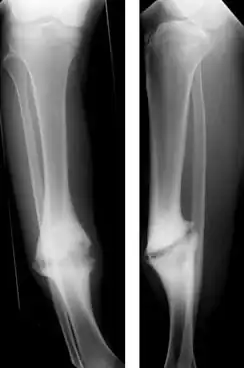

| Hypertrophic nonunion of the tibia | |

Hypertrophic non-union

Callus is formed, but the bone fractures have not joined. This can be due to inadequate fixation of the fracture, and treated with rigid immobilisation.

Judet and Judet, Muller, Weber and Cech, and others classified nonunions into two types according to the viability of the ends of the fragments: Hypervascular nonunions and avascular nonunions.

Hypervascular nonunions are subdivided as:

- "Elephant foot" nonunions: These are hypertrophic, rich in callus and are a result of inadequate immobilisation, insecure fixation or premature weight bearing.

- "Horse hoof" nonunions: Mildly hypertrophic, poor in callus and is due to unstable fixation.

- Oligotrophic nonunions: They are not hypertrophic but vascular, no callus seen and is due to severely displaced fracture or fixation without accurate apposition of fragments.

Paley classified tibial nonunions based on clinical and roentgenographic characteristics as Type A (Bone loss of less than 1 cm) and Type B (Bone loss of more than 1 cm). Type A is subclassified as Type A:1 Lax type; Lax nonunion have limited mobility and usually some fixed deformity, Type A:2:1 stiff nonunion without deformity and Type A:2:2 stiff nonunion with a deformity. Type B subclassified as Type B:1 bony defect with no shortening, Type B:2 shortening with no gap and Type B:3 there is both gap and shortening.